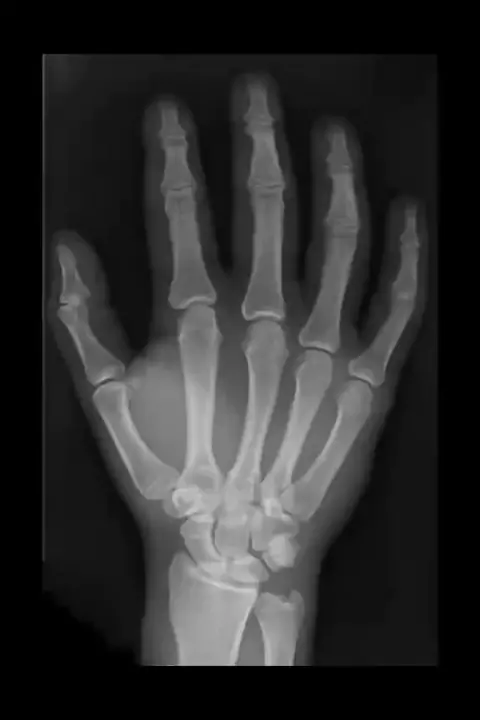

Imagens de Raio x que mostram a parte esquelética do corpo humano. #musicaepin🌃 #esqueleto #raiox #musicaepin